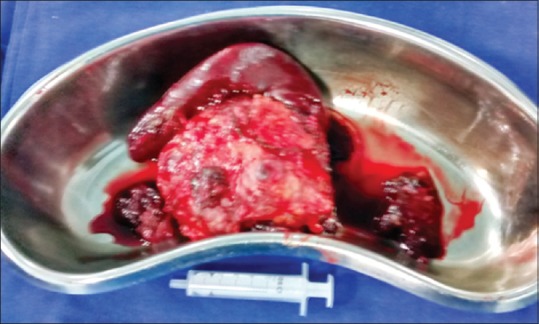

On exploratory laparotomy, a large mass was found in the lesser sac densely adherent to the pancreas and the spleen with splenic artery thrombosis. Excision of the mass [Figure 2] along with distal pancreatectomy and splenectomy was done. The postoperative course was uneventful, and the patient is doing well on follow-up.

| Figure 2:The excised specimen